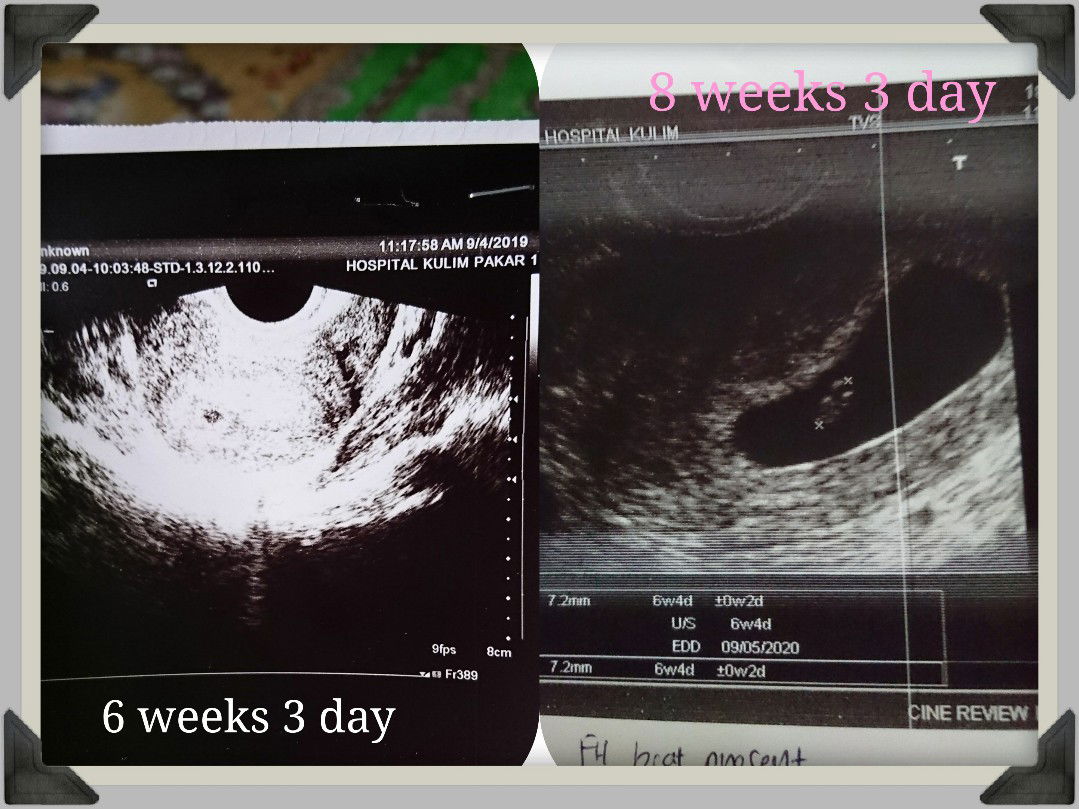

Sblum ni sy pernah share kerisauan sy tntg kandungan ethopic . actually kena warded jugak 2 hari , sbb scan tak nampak sac then doc decide untuk buat test beta Hcg . but alhamdulillah syukur 18/9 baru ni g repeat scan. Tapi disebabkan scan still nampak blur kena tvs . I can heard my baby heartbeat ?.Now dah nak masuk 9 weeks . doakan sy & kandungan sihat & selamat hingga melahirkan yaa .. #SyukurYaMujib❤